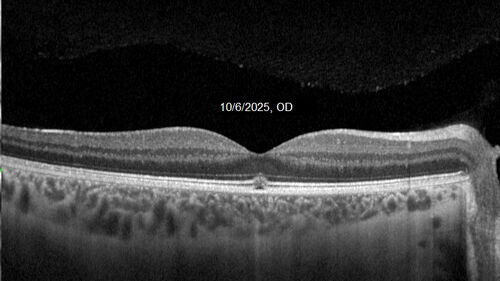

Acute Retinal Pigment Epitheliitis (Krills disease)

15 year old with sudden central vision loss in one eye. The vision loss persisted though for at least 6 months (which may be a laser injury)